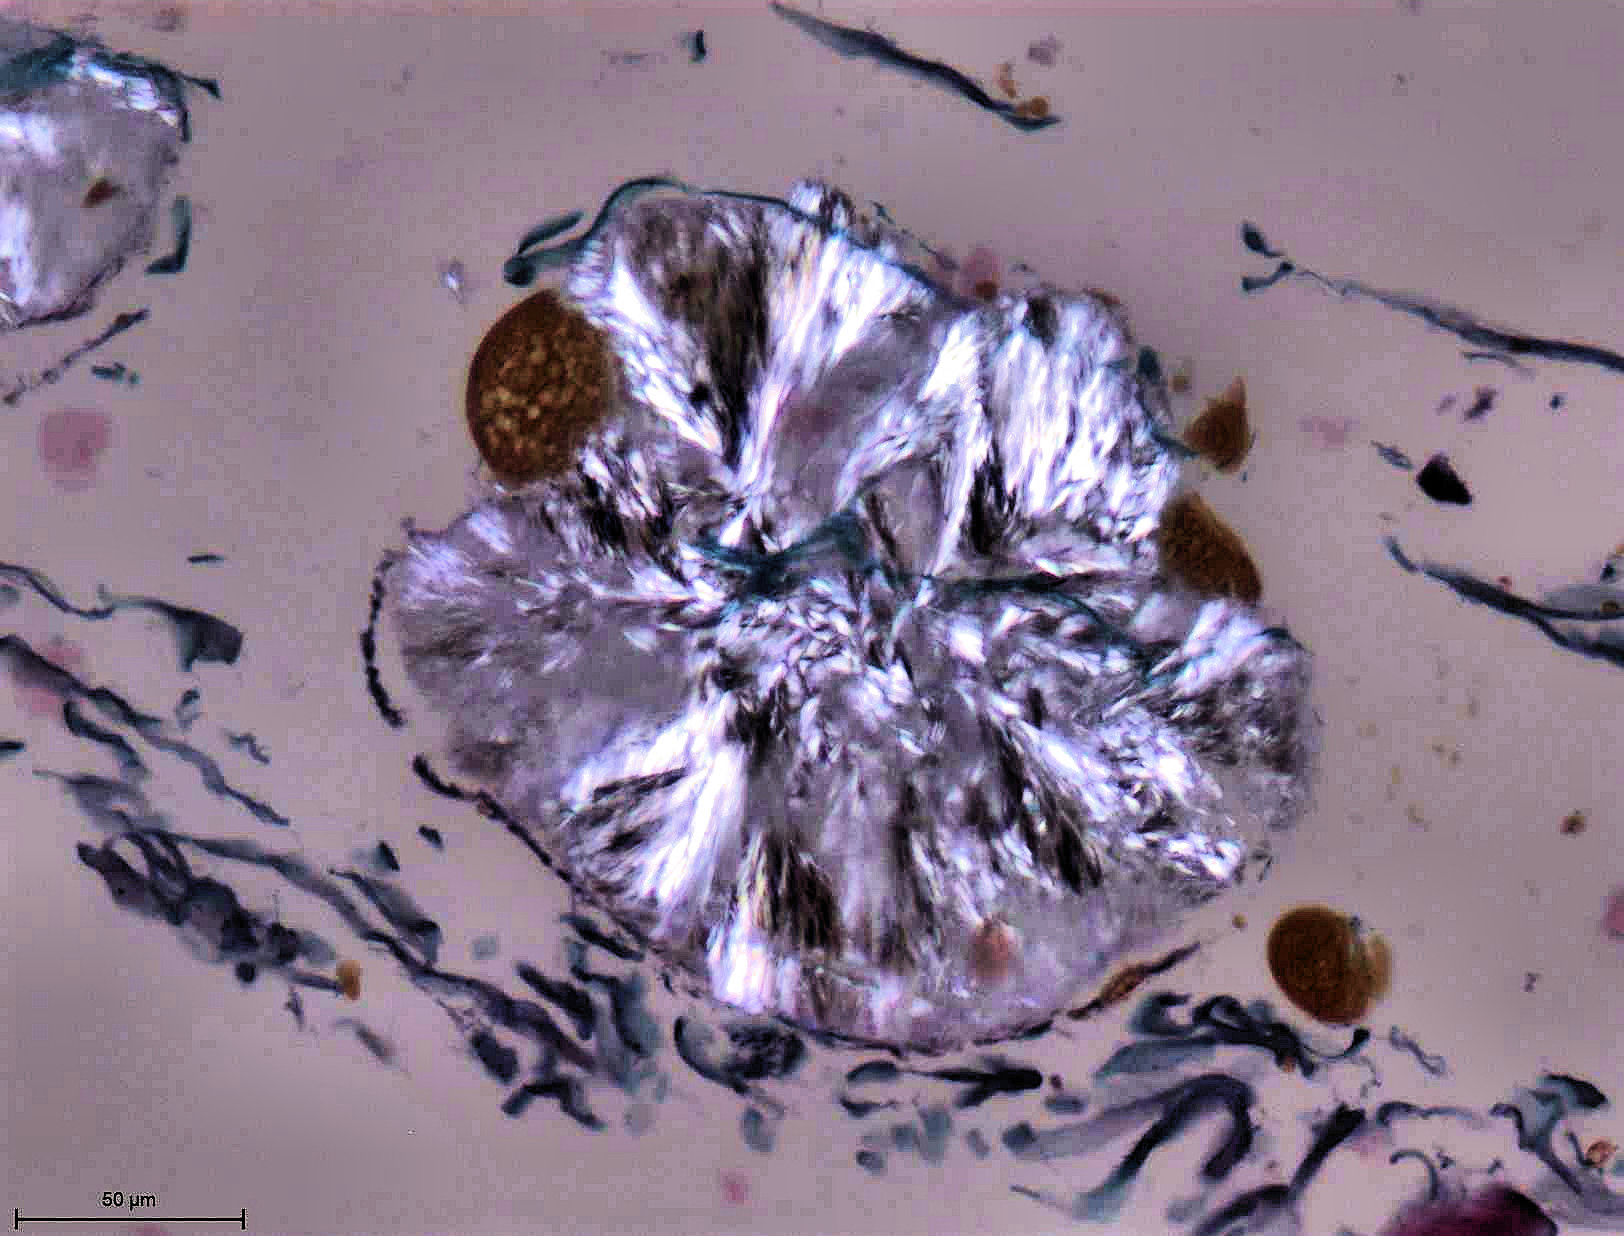

Le laboratoire d’histologie est essentiellement dédié à l’examen du squelette et des tissus mous putréfies ou momifiés dans un contexte d’anthropologie médicolégale. L'examen microscopique des tissus permet :

- de confirmer la nature humaine ou non des fragments osseux

- d’estimer le délai post mortem et donc l’origine ancienne ou récente des ossements

- de mettre en évidence la nature pathologique ou traumatique d'une lésion osseuse et d’en évaluer le délai post traumatique

- de déterminer la nature de particules exogènes animales, végétales ou autre dans des tissus putréfiés ou momifiés